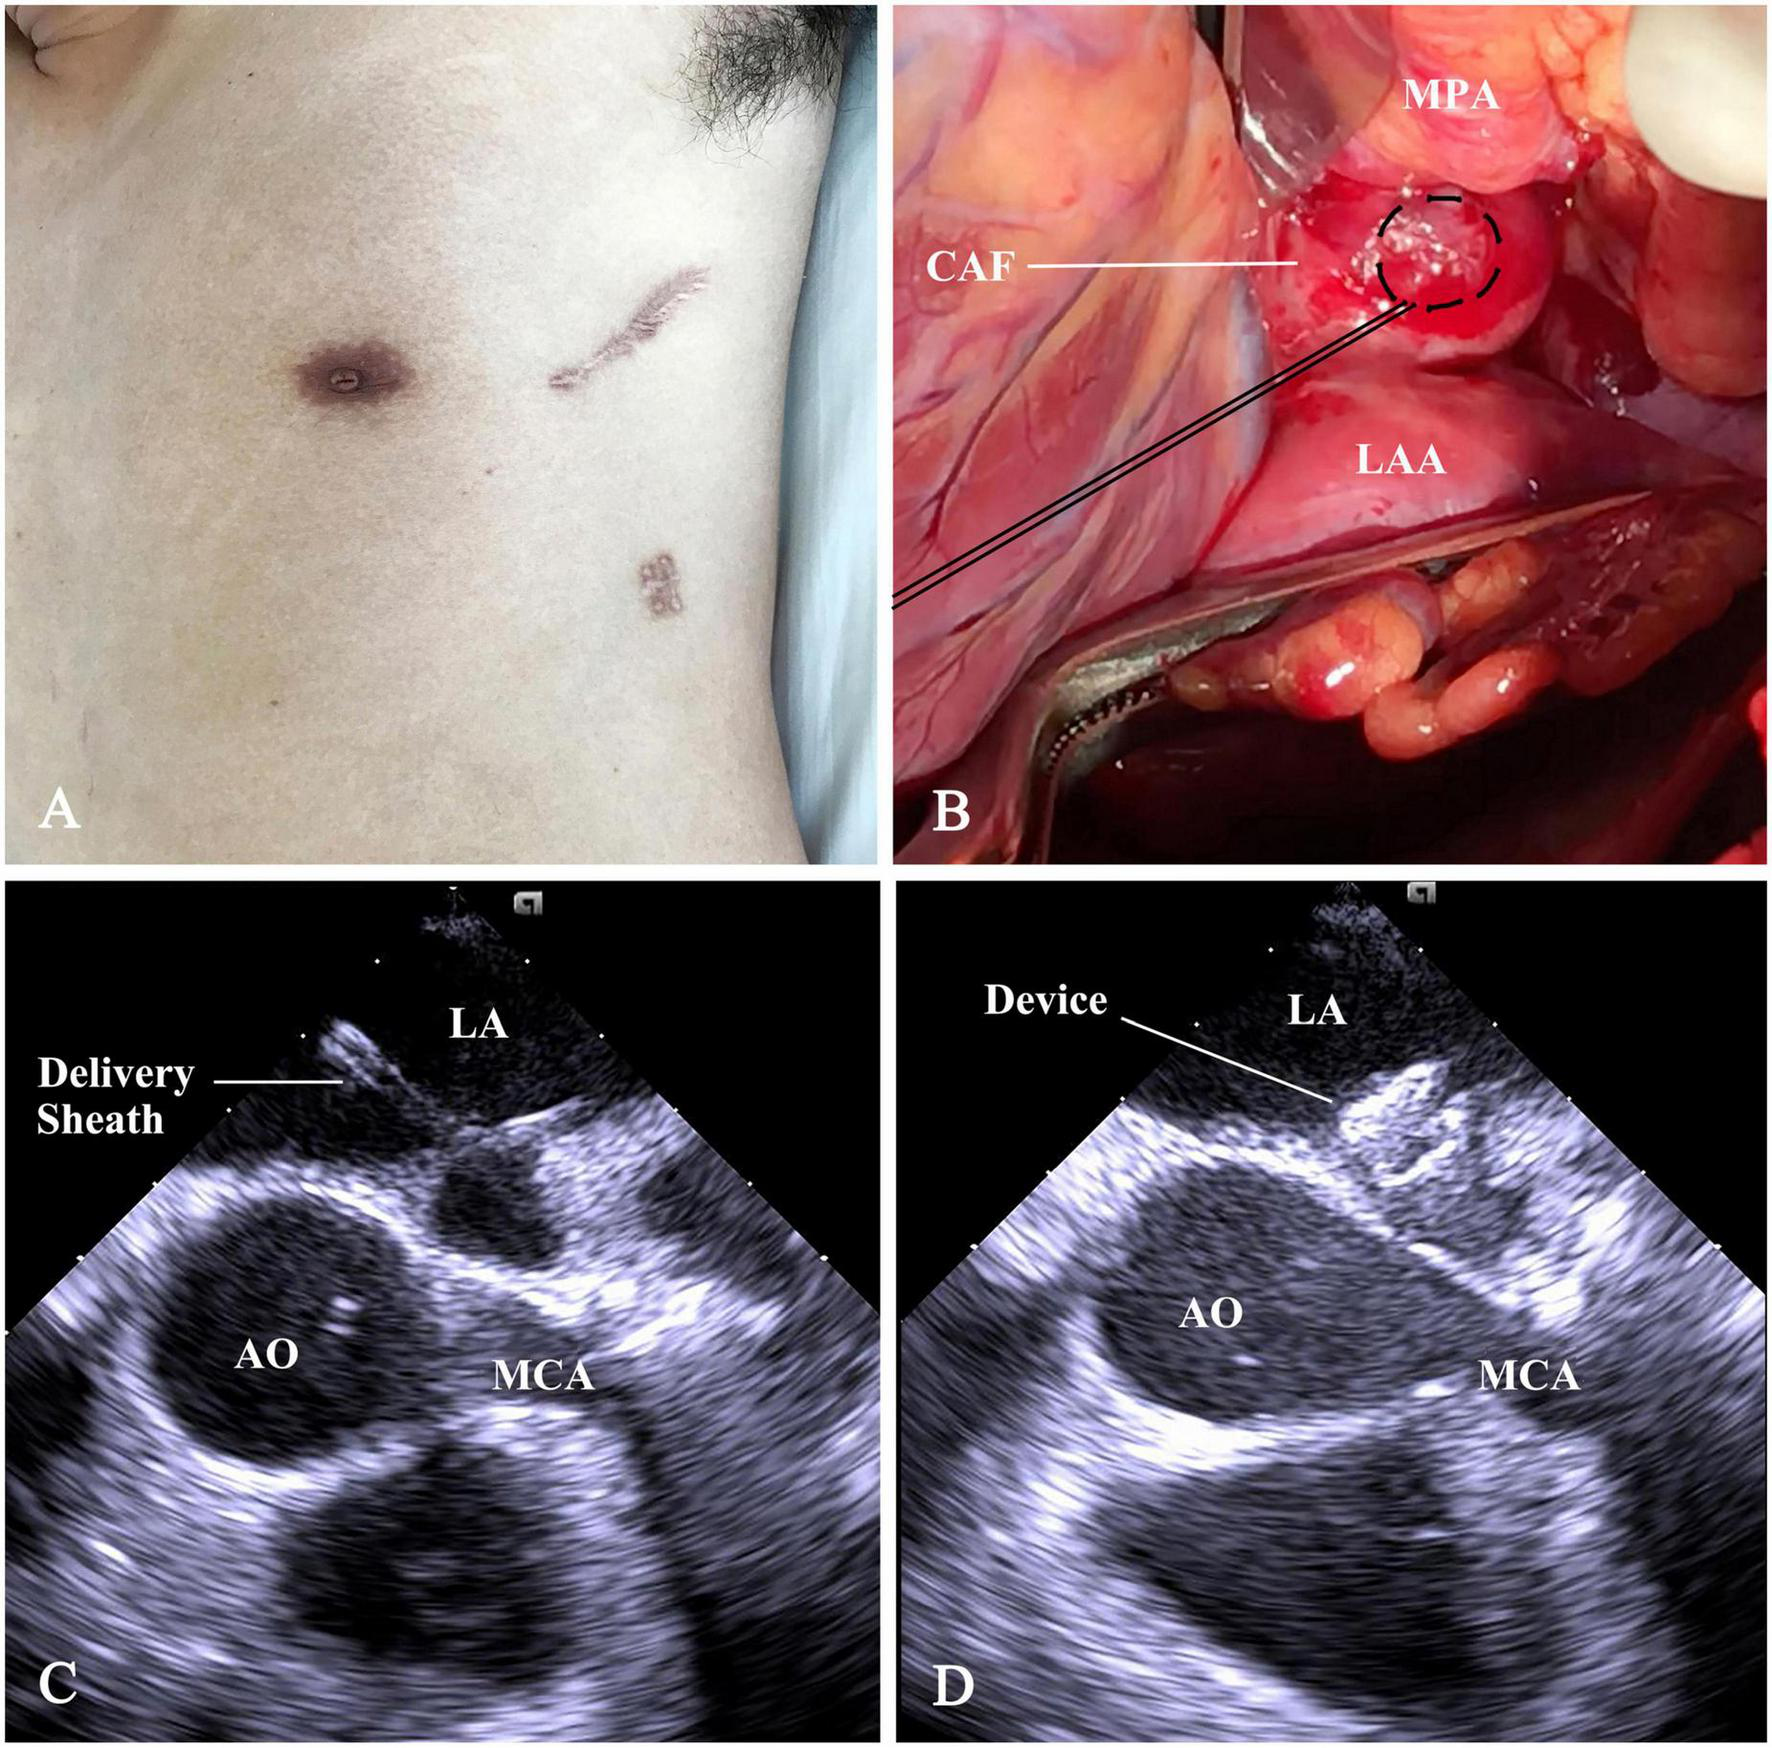

Under general anesthesia, the patient was placed in a right lateral position. A 7-cm subaxillary incision was made in the left 4th intercostal space. The pericardium was incised and cradled. An ordinary (size 8 mm) ventricular septal occluder (Starway Medical Technology, Inc, Beijing, China), connected with a stay-in suture (5-0 Polydioxanone, Ethicon, Somerville), was selected and retracted into the loading sheath. Figure 2 showed the steps of percoronary device closure of CAF. A 15-min occlusion test of CAF was well-tolerated; there was no evidence of myocardial ischemia. The occluder was scrutinized by using a push-pull maneuver repeatedly and released after satisfactory assessment. The device stay-in suture was removed before the purse-string suture snugly tied. The pericardium and incision were closed in layers with a drainage tube.

FIGURE 2

Schematic presentation of percoronary device closure of CAF. (A) The subaxillary incision. (B) The distal straight section of CAF was exposed between the main pulmonary artery (MPA), root of AO, and the LAA. A purse-string suture was placed on it. (C) Following a puncture in purse-string, a flexible guidewire was advanced into LA. Then, a 6F short delivery sheath was fed over the wire into the LA. (D) The device was deployed and positioned at the drainage orifice of the CAF. CAF, coronary artery fistula; AO, ascending aorta; LAA, left atrial appendage; LA, left atrium; MPA, main pulmonary artery; MCA, main coronary artery.